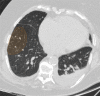

The coronavirus disease 2019 (COVID-19) pandemic is a global health care emergency. Although reverse-transcription polymerase chain reaction testing is the reference standard method to identify patients with COVID-19 infection, chest radiography and CT play a vital role in the detection and management of these patients. Prediction models for COVID-19 imaging are rapidly being developed to support medical decision making. However, inadequate availability of a diverse annotated data set has limited the performance and generalizability of existing models. To address this unmet need, the RSNA and Society of Thoracic Radiology collaborated to develop the RSNA International COVID-19 Open Radiology Database (RICORD). This database is the first multi-institutional, multinational, expert-annotated COVID-19 imaging data set. It is made freely available to the machine learning community as a research and educational resource for COVID-19 chest imaging. Pixel-level volumetric segmentation with clinical annotations was performed by thoracic radiology subspecialists for all COVID-19-positive thoracic CT scans. The labeling schema was coordinated with other international consensus panels and COVID-19 data annotation efforts, the European Society of Medical Imaging Informatics, the American College of Radiology, and the American Association of Physicists in Medicine. Study-level COVID-19 classification labels for chest radiographs were annotated by three radiologists, with majority vote adjudication by board-certified radiologists. RICORD consists of 240 thoracic CT scans and 1000 chest radiographs contributed from four international sites. It is anticipated that RICORD will ideally lead to prediction models that can demonstrate sustained performance across populations and health care systems.